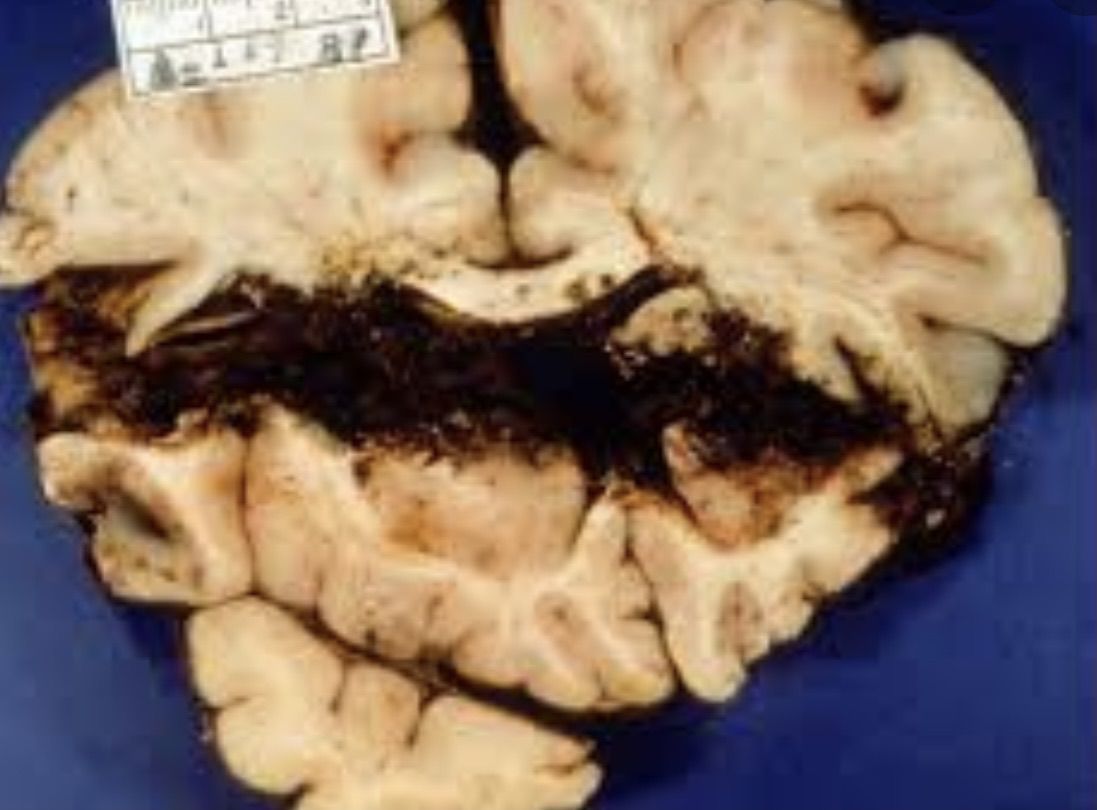

Imaging depicts an brain specimen of a gunshot wound. One can clearly see that trajectory that the bullet took. Such a catastrophe can result in an intracerebral hemorrhage, damaged pathways of the brain, injured cranial nerves (such as the optic nerve, trigeminal nerve, oculomotor nerve, etc.). Mortality is incredibly high. However, there have been reported cases where individuals have survived such events!